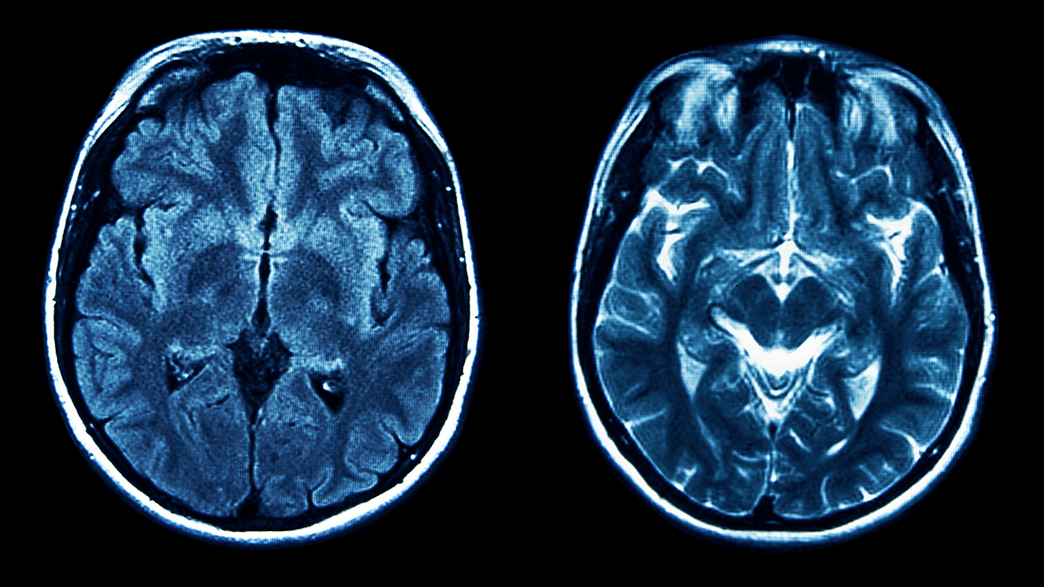

Amnesia Types Identifying Causes, Treatment